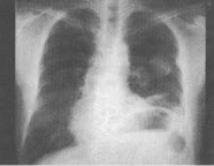

患者,男,67岁,胸痛半月余,胸片检查如图,最可能的诊断为()。

A、左上肺结核球

B、左上肺周围型肺癌

C、左上肺炎性假瘤

D、左上肺球形不张

E、左上肺脓肿

B